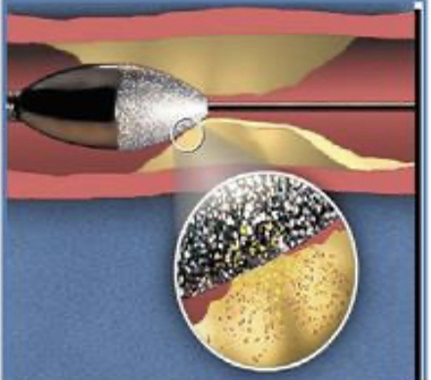

【冠脉旋磨技术】

冠脉旋磨技术是利用高速旋转的旋磨头对球囊无法扩张的内膜纤维化、钙化病变进行介入治疗的技术,被称为“血管内行走的金刚钻”。冠脉旋磨技术,使得包括左主干病变、分叉病变、严重钙化、慢性闭塞等以往常规手段无法干预的复杂病变的治疗成为可能。